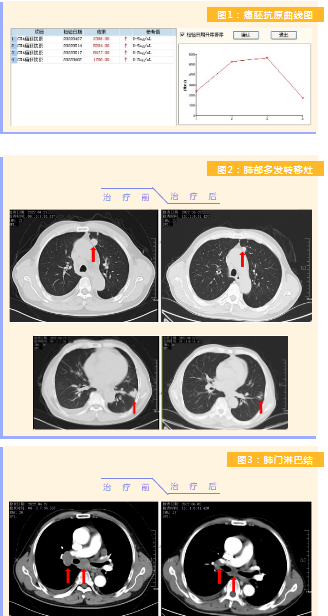

患者完成1周期治療后,上腹部疼痛癥狀基本消失,梗阻性黃疸癥狀緩解,腫瘤指標(biāo)下降(圖1),肺部多發(fā)轉(zhuǎn)移灶消失和縮?。▓D2),雙肺門淋巴結(jié)縮?。▓D3),肝臟多發(fā)轉(zhuǎn)移灶縮小(圖4)。